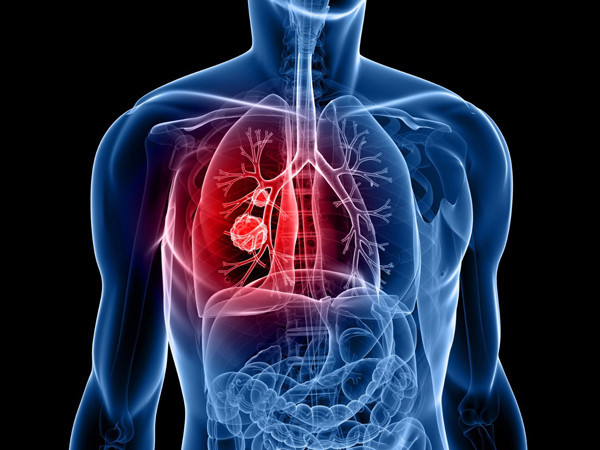

| Đến tháng 12, tình trạng sức khỏe Lý Thiến Sơn không cải thiện mà còn nặng hơn. Cô thường xuyên có cảm giác tức ngực, đau bụng. Mỗi khi ngửi mùi khói thuốc lá do chồng hút, cơn ho của Lý Thiến Sơn càng trầm trọng. (Ảnh minh họa) |

| Tranh thủ kỳ nghỉ đông, Lý Thiến Sơn đến bệnh viện địa phương khám. Kết quả ban đầu không mấy khả quan nên bác sĩ chỉ định thực hiện thêm nhiều xét nghiệm khác. Kết quả cho thấy, Lý Thiến Sơn mắc ung thư phổi. (Ảnh minh họa) |